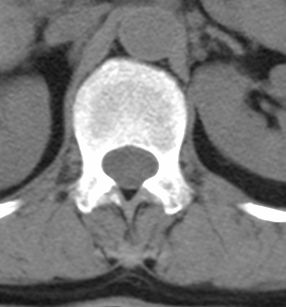

标题: CT22439:腰椎低密度病灶(腰椎血管瘤) [打印本页]

标题: CT22439:腰椎低密度病灶(腰椎血管瘤)

患者 女 54岁 外伤后检查发现l1椎体局部密度减低,请问这是什么病灶?

考虑腰椎血管瘤

椎体内部局限性骨小梁稀疏、粗大改变,周围未见软组织肿块,首先考虑椎体血管瘤。

l1椎体血管瘤可能性大;建议必要时行mri检查。